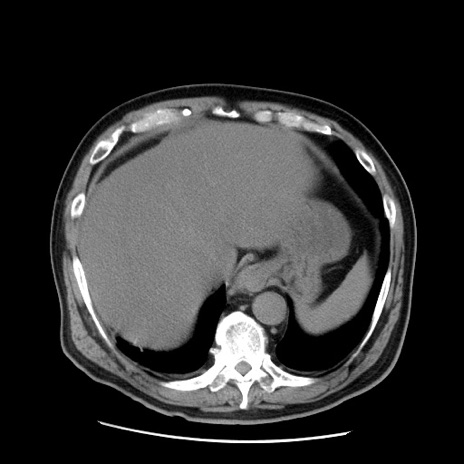

症例20(横断像)

【症例】 60歳代男性

【主訴】 腹部膨満、嘔吐

【現病歴】5日前頃より倦怠感を認め食事量減少し4日前の朝嘔吐、食事摂取困難となった。 3日前近医受診し点滴施行され整腸剤などを処方された。 当日他院を受診し、腹部膨満著明、炎症反応の上昇(CRP10.8、WBC11200)あり、紹介受診となる。

【身体所見】 意識JCS1 受け答えがはっきりしないBP 111/57mHg、 P 67bpm、、BT35.2°C、SpO2 97%(RA)、 腹部:膨隆、打診で鼓音あり、全体的に圧痛有り、腸蠕動音(-)、反跳痛ははっきりせず。

【データ】WBC 11400、CRP 14.20